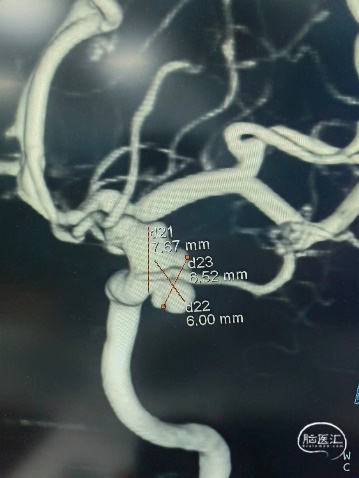

3D造影

影像显示:眼动脉段不规则动脉瘤。